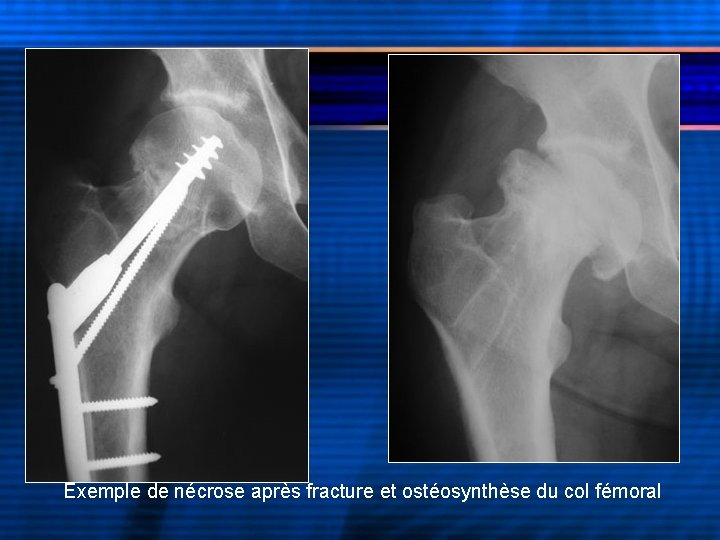

Exemple de nécrose après fracture et ostéosynthèse du col fémoral